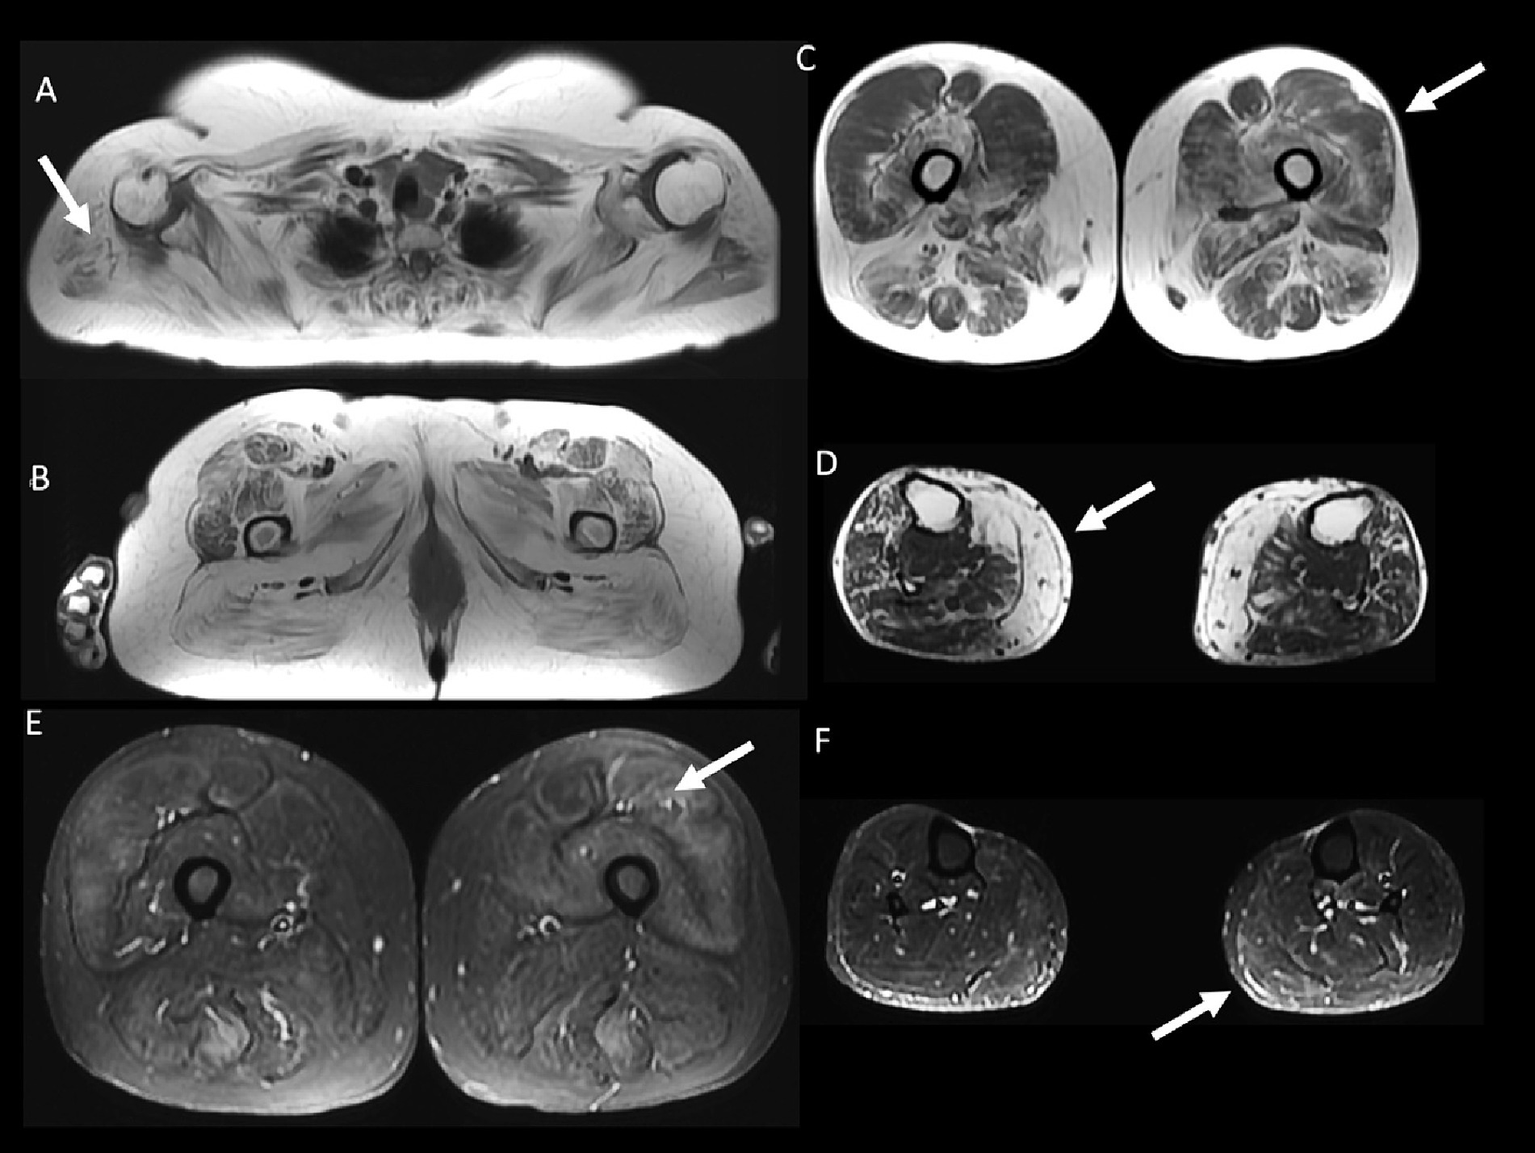

59 year-old female with inflammatory myopathy with mitochondrial pathology (IM-Mito). Axial fast spin-echo T1-weighted Whole-Body Muscle Magnetic Resonance Imaging (WBMRI) (A–D) showing severe fatty infiltration in the shoulder girdle muscles (A), moderate-severe fatty infiltration in quadriceps, gluteus and adductors muscles (B), moderate fatty infiltration in quadriceps muscle with relatively spared rectus femoris muscle compared to other quadriceps muscles (C) and severe fatty infiltration in the medial gastrocnemius muscle (D). Axial STIR WBMRI shows quadriceps muscle edema (E) and gastrocnemius muscle edema (F).

Other general radiological findings are shown in Table 7. Muscle edema in at least one muscle was found in most patients with IM-Mito and IBM (Figure 5), but there was no significant difference between the two groups. The mean number of muscles with edema per patient was also similar between the two groups. Asymmetry was observed in most study participants; however, there was no statistically significant difference between patients with IM-Mito and IBM. Most participants with IM-Mito and IBM showed relatively spared rectus femoris muscle compared to other quadriceps muscles (Figure 4). Nevertheless, no statistically relevant difference was found between the groups. The most compromised upper limb muscle by edema or fatty infiltration in patients with IM-Mito and IBM was the flexor digitorum profundus (Figure 6). Although not statistically significant, there was a trend towards greater radiological involvement of these muscles in individuals with IBM compared to those with IM-Mito (100% vs. 64.3%, respectively, p = 0.05).

Heatmap evaluation showed that muscles with the highest mean degree of fatty infiltration in WBMRI were quadriceps and medial gastrocnemius in both groups of patients (Figures 2–4). There was no statistically significant difference in the mean degree of fatty infiltration of the various muscles evaluated in patients with IM-Mito and IBM (Table 6). We highlight a trend for patients with IBM to have a higher mean number of muscles with fatty infiltration when compared with IM-Mito (37.9 and 24.6, respectively, p = 0.05).